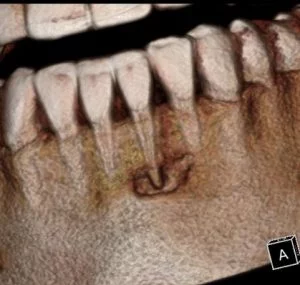

A CBCT was taken after a negative cold test indicated a necrotic tooth.  When the CBCT was taken, we could clearly see that the abscess had completely perforated the labial bone at the apex of #24 and was close to doing so on #25.

As we investigated more deeply, we identified another critical piece of information that would affect our treatment plan: a second canal on #24.

Had I initiated treatment on this particular tooth and kept my access very conservative, there’s a chance I would have missed the other canal. Furthermore, had I started the treatment and then found the second canal after access into the chamber, I would have had to spend time determining the anatomy of both canals.  For example, I would have had to determine if they had separate apicies.